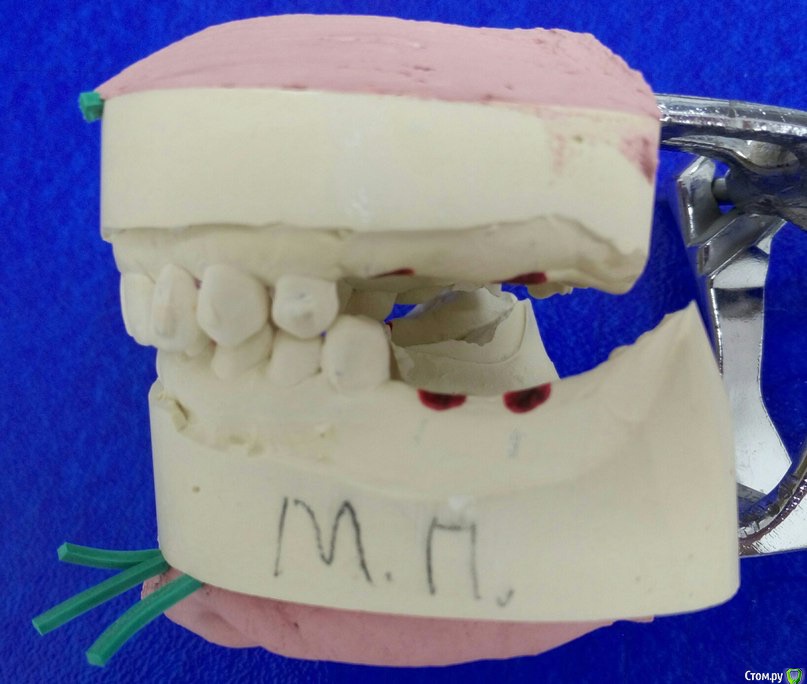

Доброго времени суток коллеги, сразу извиняюсь за качество фото т.к. фотографировал на тапок. Вот такая ситуэшн, на днях ко мне попала пациент от коллеги с окклюдатором в руках, где загипсованы модели в привычном прикусе. Там где отмечены красные точки, стоят уже формирователи. Сделал оптг, забрал модели.

На сегодня имеем феномен Попова-Годона в области 1.6, 1,7, стираемость нижних резцов, глубокое резцовое перекрытие. Думаю, что все это связано с длительным отсутствием жевательных зубов.

По снимку явно дегенеративные изменения сустава, бугорка почти нет, поэтому я думаю можно было бы, для начала попытаться поднять высоту на имплантах используя временные абатменты и времянки. Сможете поднять прикус на необходимую высоту + частично попытаться устранить феномен попова-годона (если зубы оставлять), за одно понаблюдаете, как на это отреагирует сустав. На мой взгляд при таком состоянии сустава даже с лицевой дугой будет проблематично идеальное определение ЦС ИМХО. Все остальное на времянках думаю до года. И на ОПТГ надо было сережки снять :rolleyes:  ;) . Можно сразу уменьшить высоту 1.6,1.7, учитывая карман глубокий за 1.7, а можно все их убрать (1.9,1.8,1.7,1.6) и поставить импланты(меньше геморроя) :)